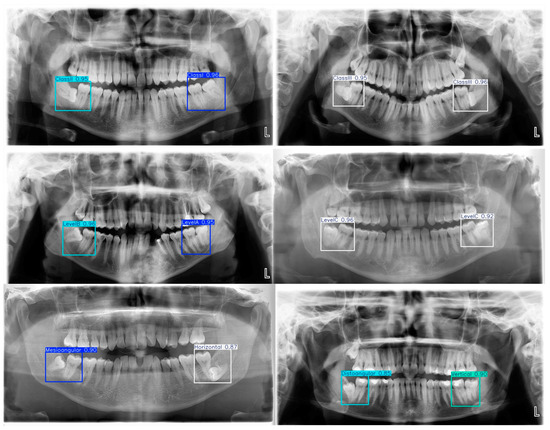

Artificial intelligence (AI) has significantly transformed the field of dentomaxillofacial radiology, improving the diagnostic accuracy. AI algorithms have been developed to efficiently analyze and interpret complex medical and dental images, enabling faster and more precise detection of dental and maxillofacial pathologies. By leveraging deep learning and machine learning techniques, AI systems can detect abnormalities such as caries, fractures, and tumors with higher sensitivity and specificity, in addition to hidden aspects such as aspects of shape, intensity and texture in the images. Therefore, this Special Issue is focused on the latest developments of AI in dentomaxillofacial radiology, encompassing insights of computer-aided diagnosis, radiomics and machine learning tools for image interpretation.